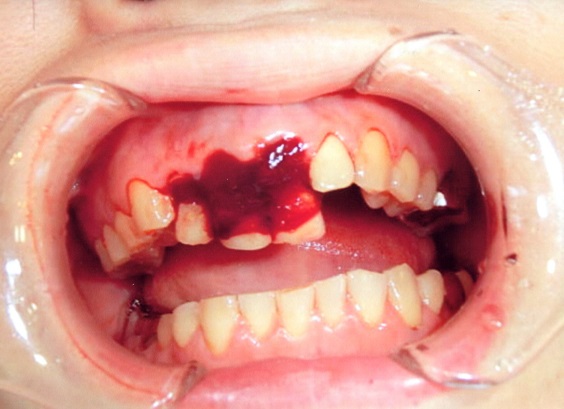

症例1

下顎前歯5本に相当する歯槽骨骨折。

歯牙の変位が著しく、整復し、矯正用器材で固定しました。